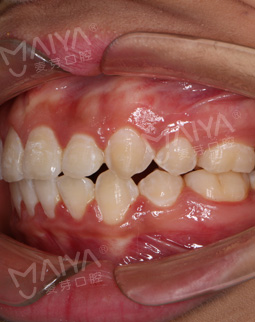

“对比第一次矫牙,我的变化还是很明显的对吧,哈哈,看到侧貌的变化,我真的乐坏了!感谢麦芽口腔,侧貌的线条真的精致了很多,之前嘴巴和下颌都外凸,现在都收回去了,比心麦芽口腔。明明是想通过矫正变美,却因错误的选择而受罪。”

“发现自己的脸型越发前突之后,我做的第一件事就是找个靠谱的口腔机构,重新矫正牙齿,当时满脑子想的就是,钱已经不重要了,就希望脸型能扭转过来,满心后悔自己当初的选择,强烈呼吁想矫牙的妹子们,别觉得牙齿矫正就只看价格,真的,医生的技术实在太重要了。鉴于第一次的情况,我重新选择机构的时候,特别看重医生的过往矫牙病例,除此之外,还多方打听对比看医院的口碑和规模,最后选择了麦芽口腔。”